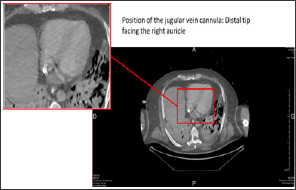

g) In parallel to branching the venous line on the femoral vein cannula, while the former circuit is clamped, the jugular vein cannula is disconnected, purged with water and then reconnected to the new circuit (Figure 3).

Figure 3: Thoracic-abdominal-pelvic CT scan with injection, portal-venous phase. Position of the jugular vein cannula.